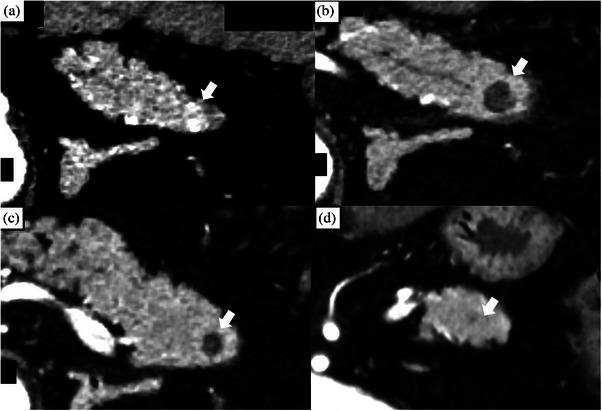

内镜超声引导下射频消融治疗小胰腺神经内分泌肿瘤的疗效与安全性:一项前瞻性试点研究。

Efficacy and safety of endoscopic ultrasonography-guided radiofrequency ablation of small pancreatic neuroendocrine neoplasms: A prospective, pilot study.

Endoscopic ultrasonography (EUS)-guided radiofrequency ablation has recently been introduced as one of the management strategies for small pancreatic neuroendocrine neoplasms (PNENs). However, prospective data on its safety and efficacy remain limited.

METHODS

This prospective pilot study was conducted at Okayama University Hospital from May 2023 to December 2024. Patients with grade 1 PNENs ≤15 mm, confirmed by EUS-guided fine-needle aspiration, were included. The primary endpoint was safety (adverse events [AEs] evaluated according to the 2010 guidelines of the American Society for Gastrointestinal Endoscopy. Severe AEs were defined as moderate or higher in American Society for Gastrointestinal Endoscopy grading and grade ≥3. Secondary endpoints included efficacy (complete response on contrast-enhanced computed tomography at 1 and 6 months), treatment details, device failure, diabetes mellitus exacerbation, and overall survival at 6 months.

RESULTS

Five patients with non-functional PNENs (median age: 64 years; median tumor size: 10 mm) were treated. AEs occurred in two patients (40%, 2/5), although none was severe. Both patients developed asymptomatic pseudocysts, one experienced mild pancreatitis, and both resolved with conservative treatment. The complete response rates on contrast-enhanced computed tomography at one and 6 months were 100%. The median procedure time was 16 min without any device failure, and the median hospitalization was 5 days. None of the patients developed new-onset or worsening diabetes mellitus. The 6-month overall survival rate was 100%.

CONCLUSION

EUS-guided radiofrequency ablation demonstrated a high complete response rate with no severe AEs in this pilot study, suggesting a minimally invasive option for small, low-grade PNENs (jRCTs062230014).